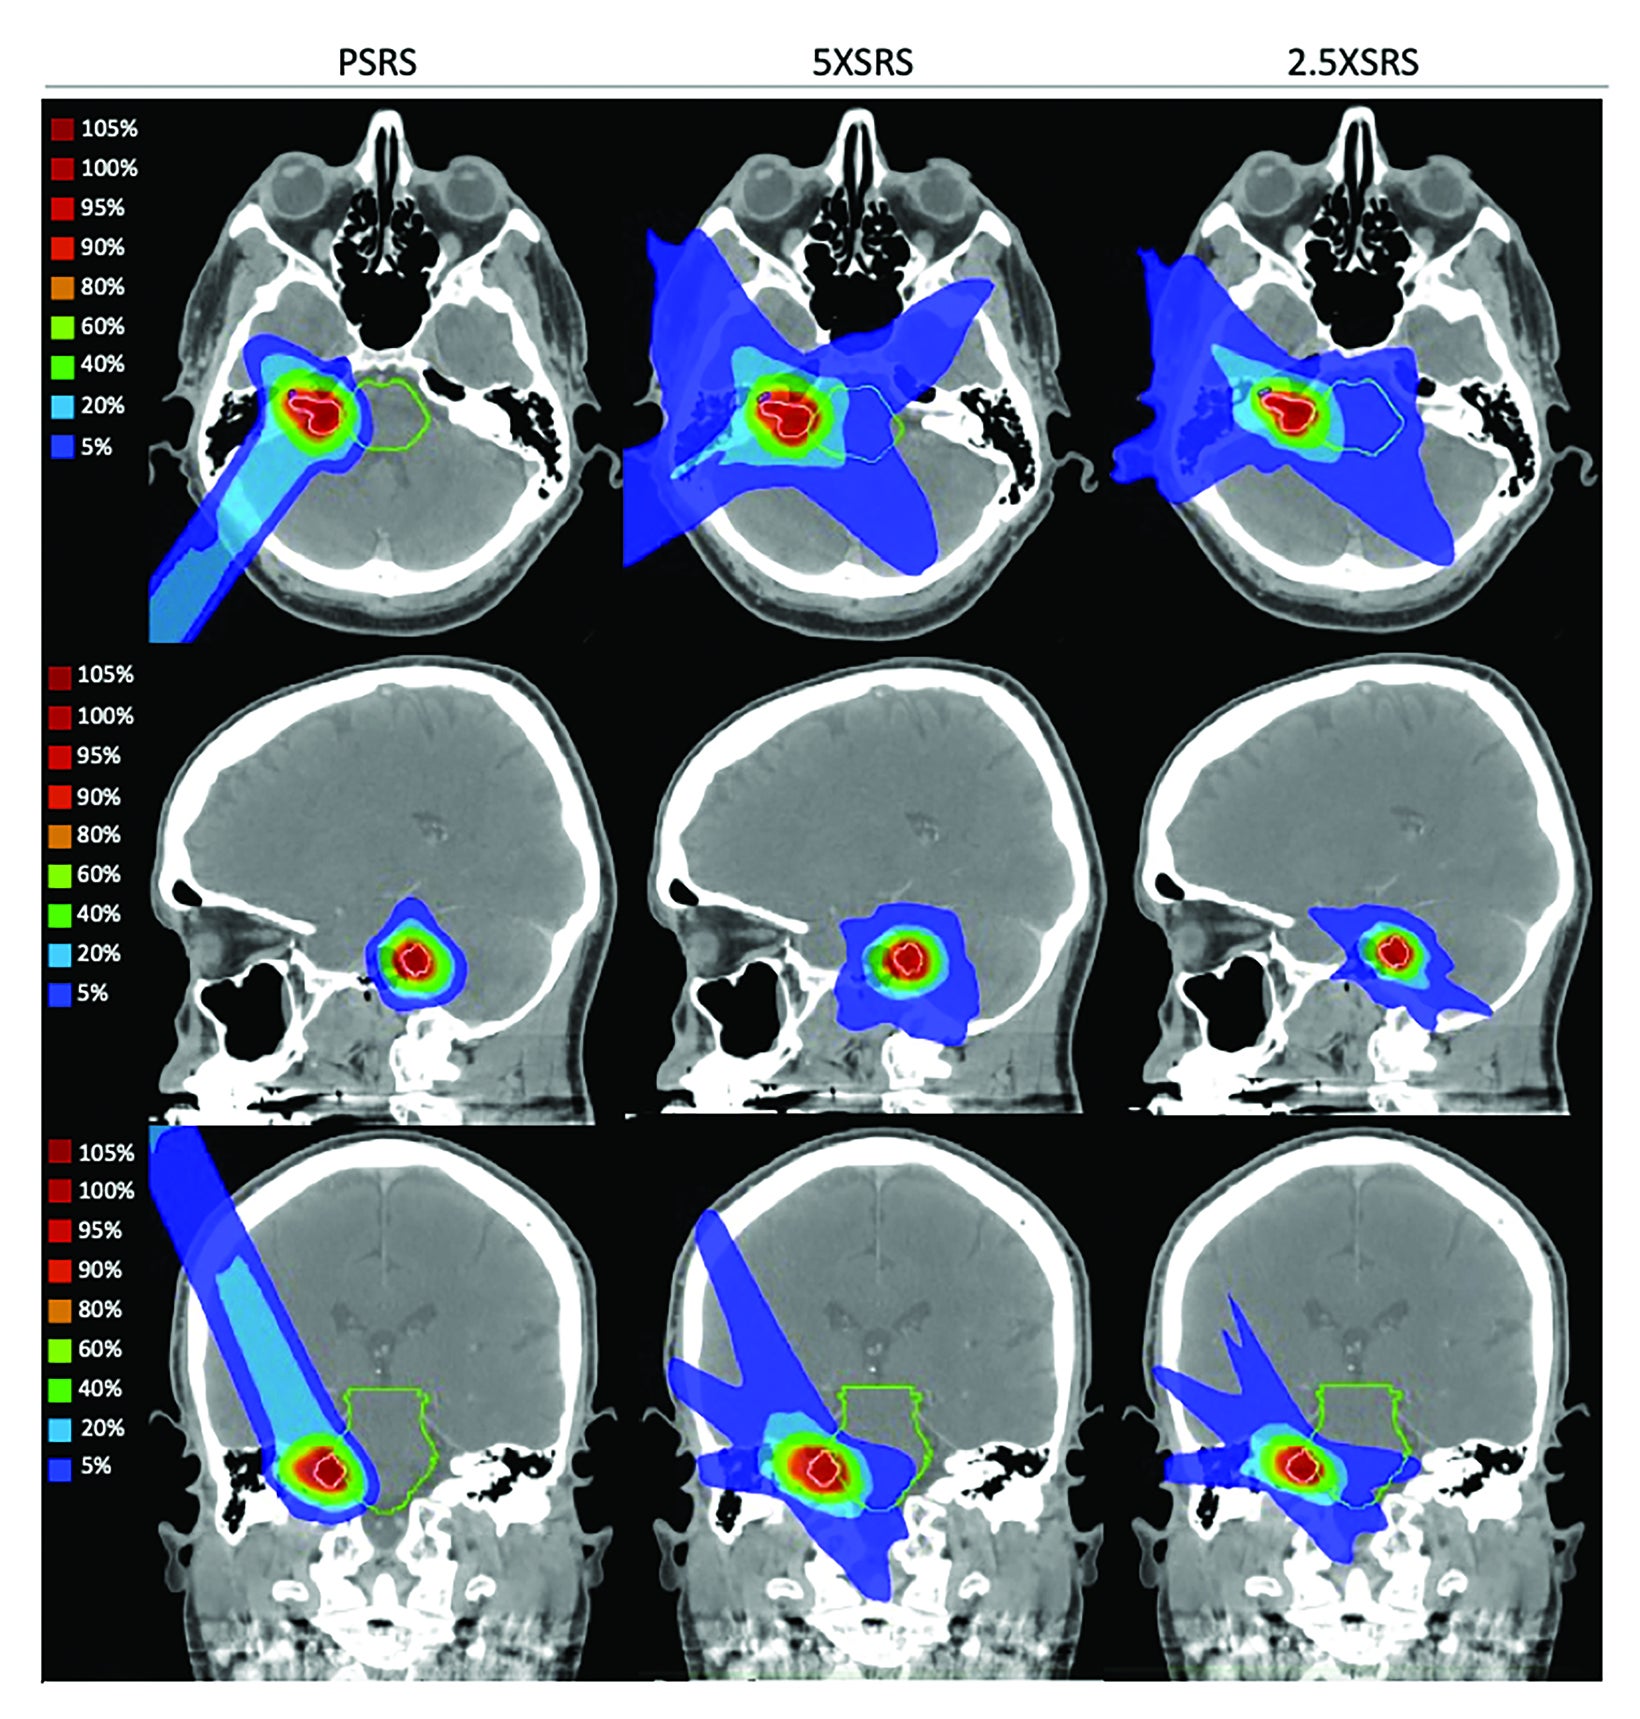

La radiocirugía utiliza radiación altamente dirigida para tratar una lesión específica, por ejemplo, tumores pequeños, malformaciones vasculares o metástasis, con la intención de controlar su crecimiento o inducir cambios que reduzcan su actividad. A diferencia de una cirugía convencional, el efecto no siempre es inmediato. En muchos casos, el resultado ocurre de manera progresiva en semanas o meses, mientras el tejido tratado responde al impacto de la radiación.

Por esa razón, los cuidados posteriores se enfocan en controlar inflamación, prevenir complicaciones, manejar efectos secundarios y sostener un monitoreo clínico e imagenológico. Entender esto ayuda a disminuir la ansiedad, ya que el paciente sabe que “sentirse normal” el mismo día no invalida el tratamiento, y que también es normal que los cambios se observen en el seguimiento.

Seguimiento y estudios de control después de la radiocirugía

Una parte esencial de los cuidados posteriores es el seguimiento. La radiocirugía requiere controles clínicos para evaluar síntomas y, en muchos casos, estudios de imagen a mediano plazo para observar la evolución. Es importante saber que los cambios en la lesión no siempre son inmediatos. Puede haber inflamación transitoria o modificaciones en la apariencia del tejido tratado que se interpretan dentro del contexto clínico.